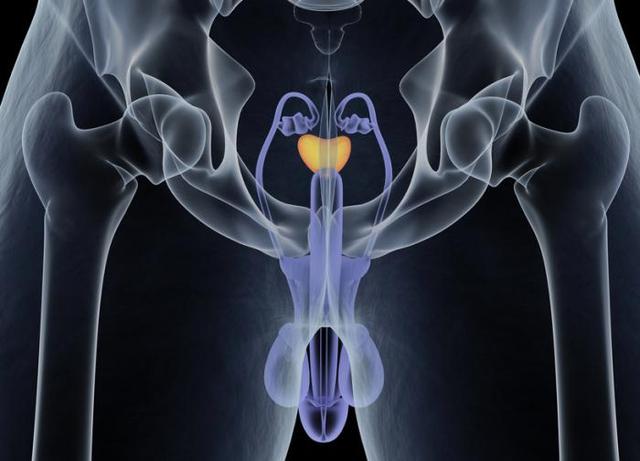

上廁所時出現這7個症狀,小心前列腺癌

前列腺癌是男性常見的癌症之一,但和其他大多數癌症一樣,由於疾病發展緩慢,剛開始的時候可能沒有任何跡象,或者你根本注意不到這些跡象。

但是,當前列腺大到影響尿道時,症狀會變得明顯。這時候,你可能會開始注意到症狀,其中大部分與你上廁所的表現有關。從排尿需求增加到排尿困難,下面有7個症狀需要注意,它們包括: